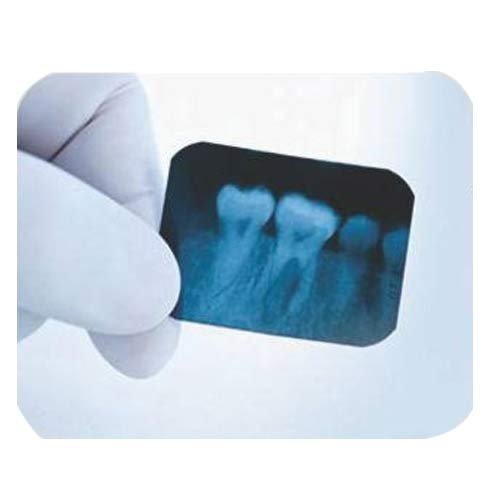

The ECO-30 is intended to provide fast, high-resolution x-rays without the use of a dental processor.

- The ECO-30 is intended to provide fast, high-resolution x-rays without the use of a dental processor.

- Available as a self-contained packet with a mono bath solution in one end and an adult size film in the other, the ECO-30 x-ray is fully developed in 50 seconds.

- Self-developing, high definition x-ray films.